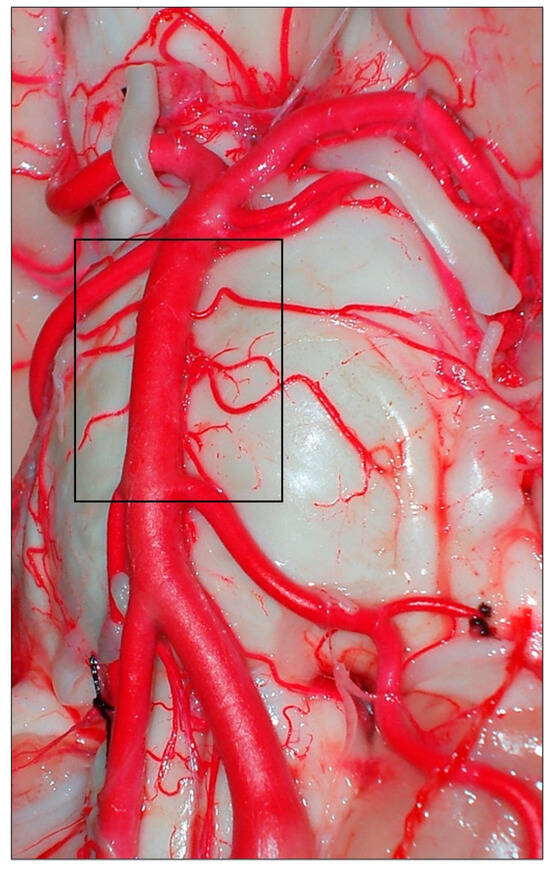

Figure 1. Vertebrobasilar arterial trunk: panoramic view. PCA, posterior cerebral artery; SCA, superior cerebellar artery; AICA, anterior inferior cerebellar artery; VA, vertebral artery; BA, basilar artery; ASA, anterior spinal artery; PICA, posterior inferior cerebellar artery; III, oculomotor nerve; VI, abducens nerve; VII, facial nerve; VIII, vestibulocochlearis nerve; X, vagus nerve.

The basilar extends superiorly from its origin next to the bulbopontine junction to its terminal bifurcation into the two posterior cerebral arteries. In 92% of cases, the terminal bifurcation of the BA is located in the interpeduncular cistern adjacent to the dorsum sellae or in the suprasellar cistern below the level of the floor of the third ventricle. The BA normally measures 32 mm in length and 3–4 mm in diameter [35].

The BA has labyrinthine, perforating (little studied), cerebellar, and hemispheric cerebral branches [36]. The BA may have some anatomical variants: The anterior inferior cerebellar artery (AICA) may share a common origin with the posterior inferior cerebellar artery (PICA) or originate from a single trunk, forming in this case the AICA-PICA trunk. The PICA, which usually originates from the vertebral artery, may vascularize the entire territory of the AICA, with the opposite also occurring on some occasions. An accessory AICA can supplement or replace part of the normal distribution of the AICA, a fact that is identified in 20% of anatomical dissections. Multiple superior cerebellar arteries (SCAs) are also frequent: a double SCA may be present in 8% or a triple SCA in 2% instead of a single dominant trunk [37]. Segmental hypoplasia of one or more of the vertebrobasilar components is not uncommon. If there is a fetal origin of the posterior cerebral artery (PCA) supplied from the anterior circulation, the BA appears to end up bifurcating into the SCAs. Duplication of the BA is associated with duplication of the pituitary gland in rare cases [2,38].